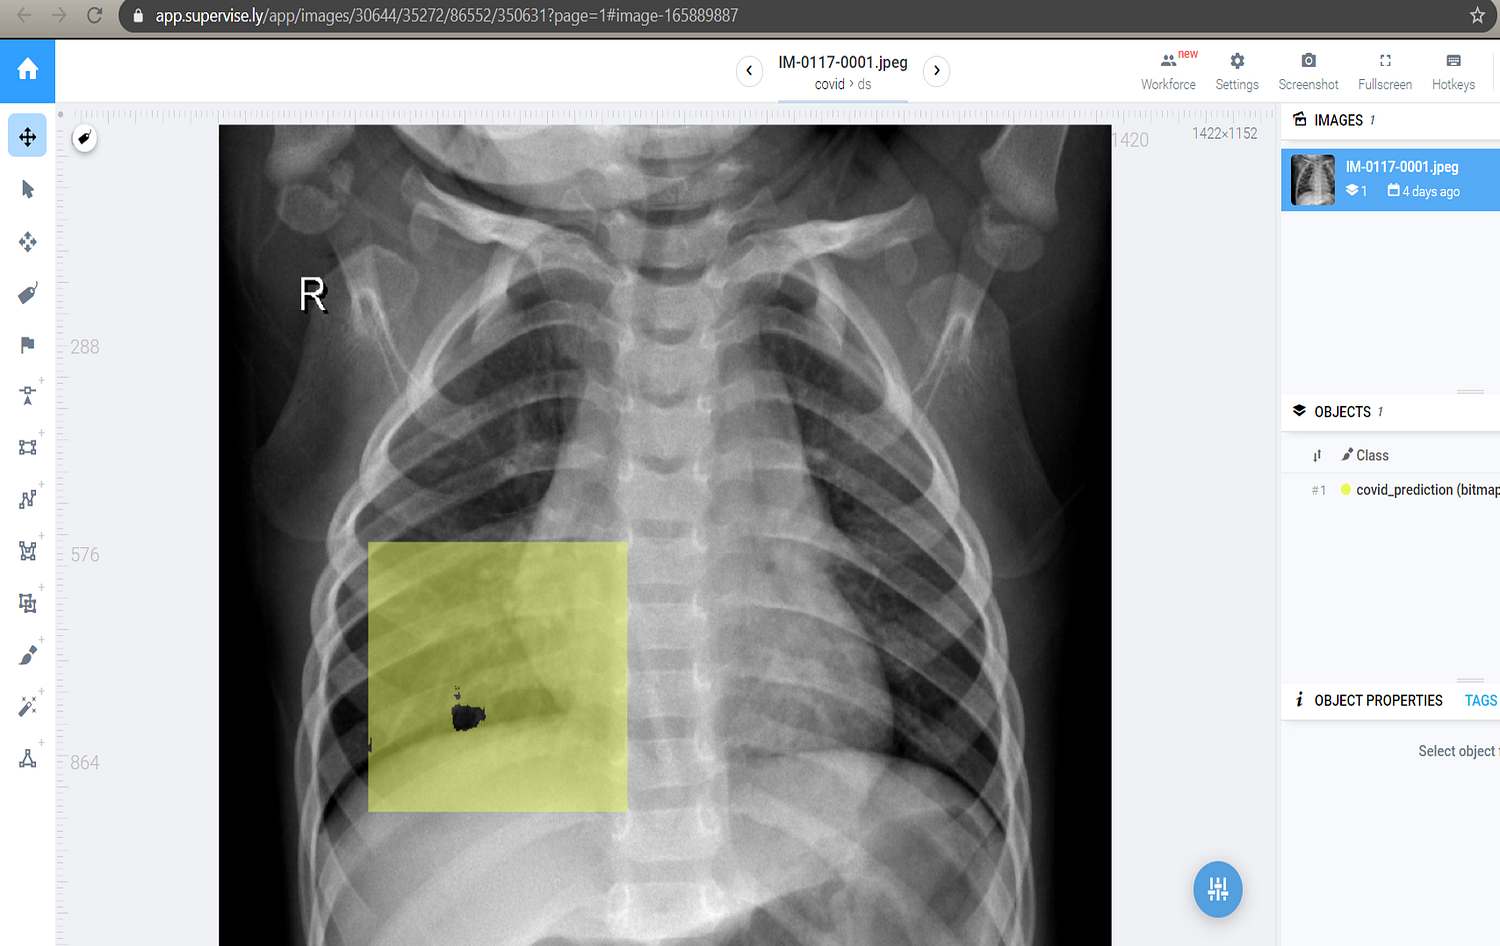

After creating the project and uploading the images, we need to annotate the images, so that our model knows what exactly to look in the images.

After downloading the weights file, we update the Mask RCNN demo code available at Matterplot Repository accordingly to accept this weight file.

Thus by the above process, we were able to perform instance segmentation on COVID Chest X-Rays. Our model confirmed that the X-ray provided was having Ground Glass Opacities, which in turn predicted that the associated person might be infected.

By more proper annotations on the training images, we can increase the accuracy of the model so that it can mask the exact area of the GGOs in the future. Moreover, we can provide a powerful remote instance having GPUs, which can automate the entire process remotely, rather than testing the weights manually.